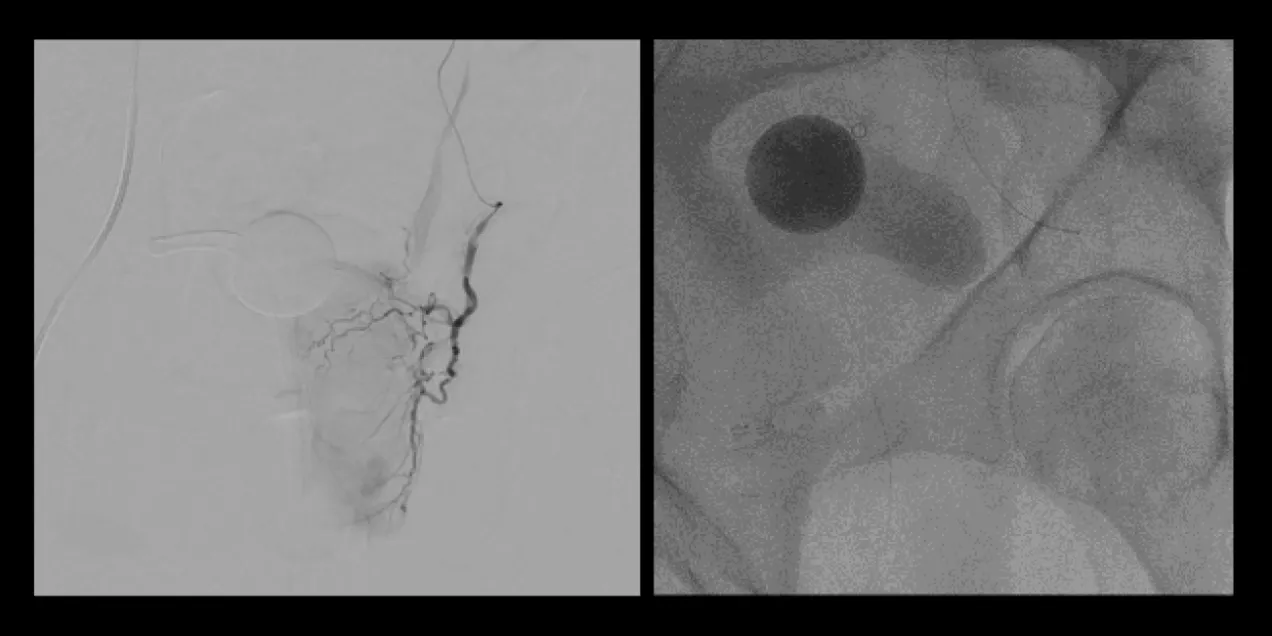

side-by-side fluoroscopic images showing pelvic vascular anatomy; the left panel displays a contrast-filled arterial tree with catheter in place, and the right panel shows a round radiopaque marker and surrounding bony structures during prostate artery embolization

picture 2Overall, the procedure involves shrinking the prostate by treating its blood vessels. An interventional radiologist gains access through a small incision in the upper thigh or the wrist. From there, small particles are injected into the prostate to slow the blood flow to the gland, causing the prostate to shrink. Relief from BPH symptoms occurs in the following weeks and months. It is a relatively painless procedure using conscious sedation. After the procedure, UCSF Radiology follows up with patients at one, six and 12 months.